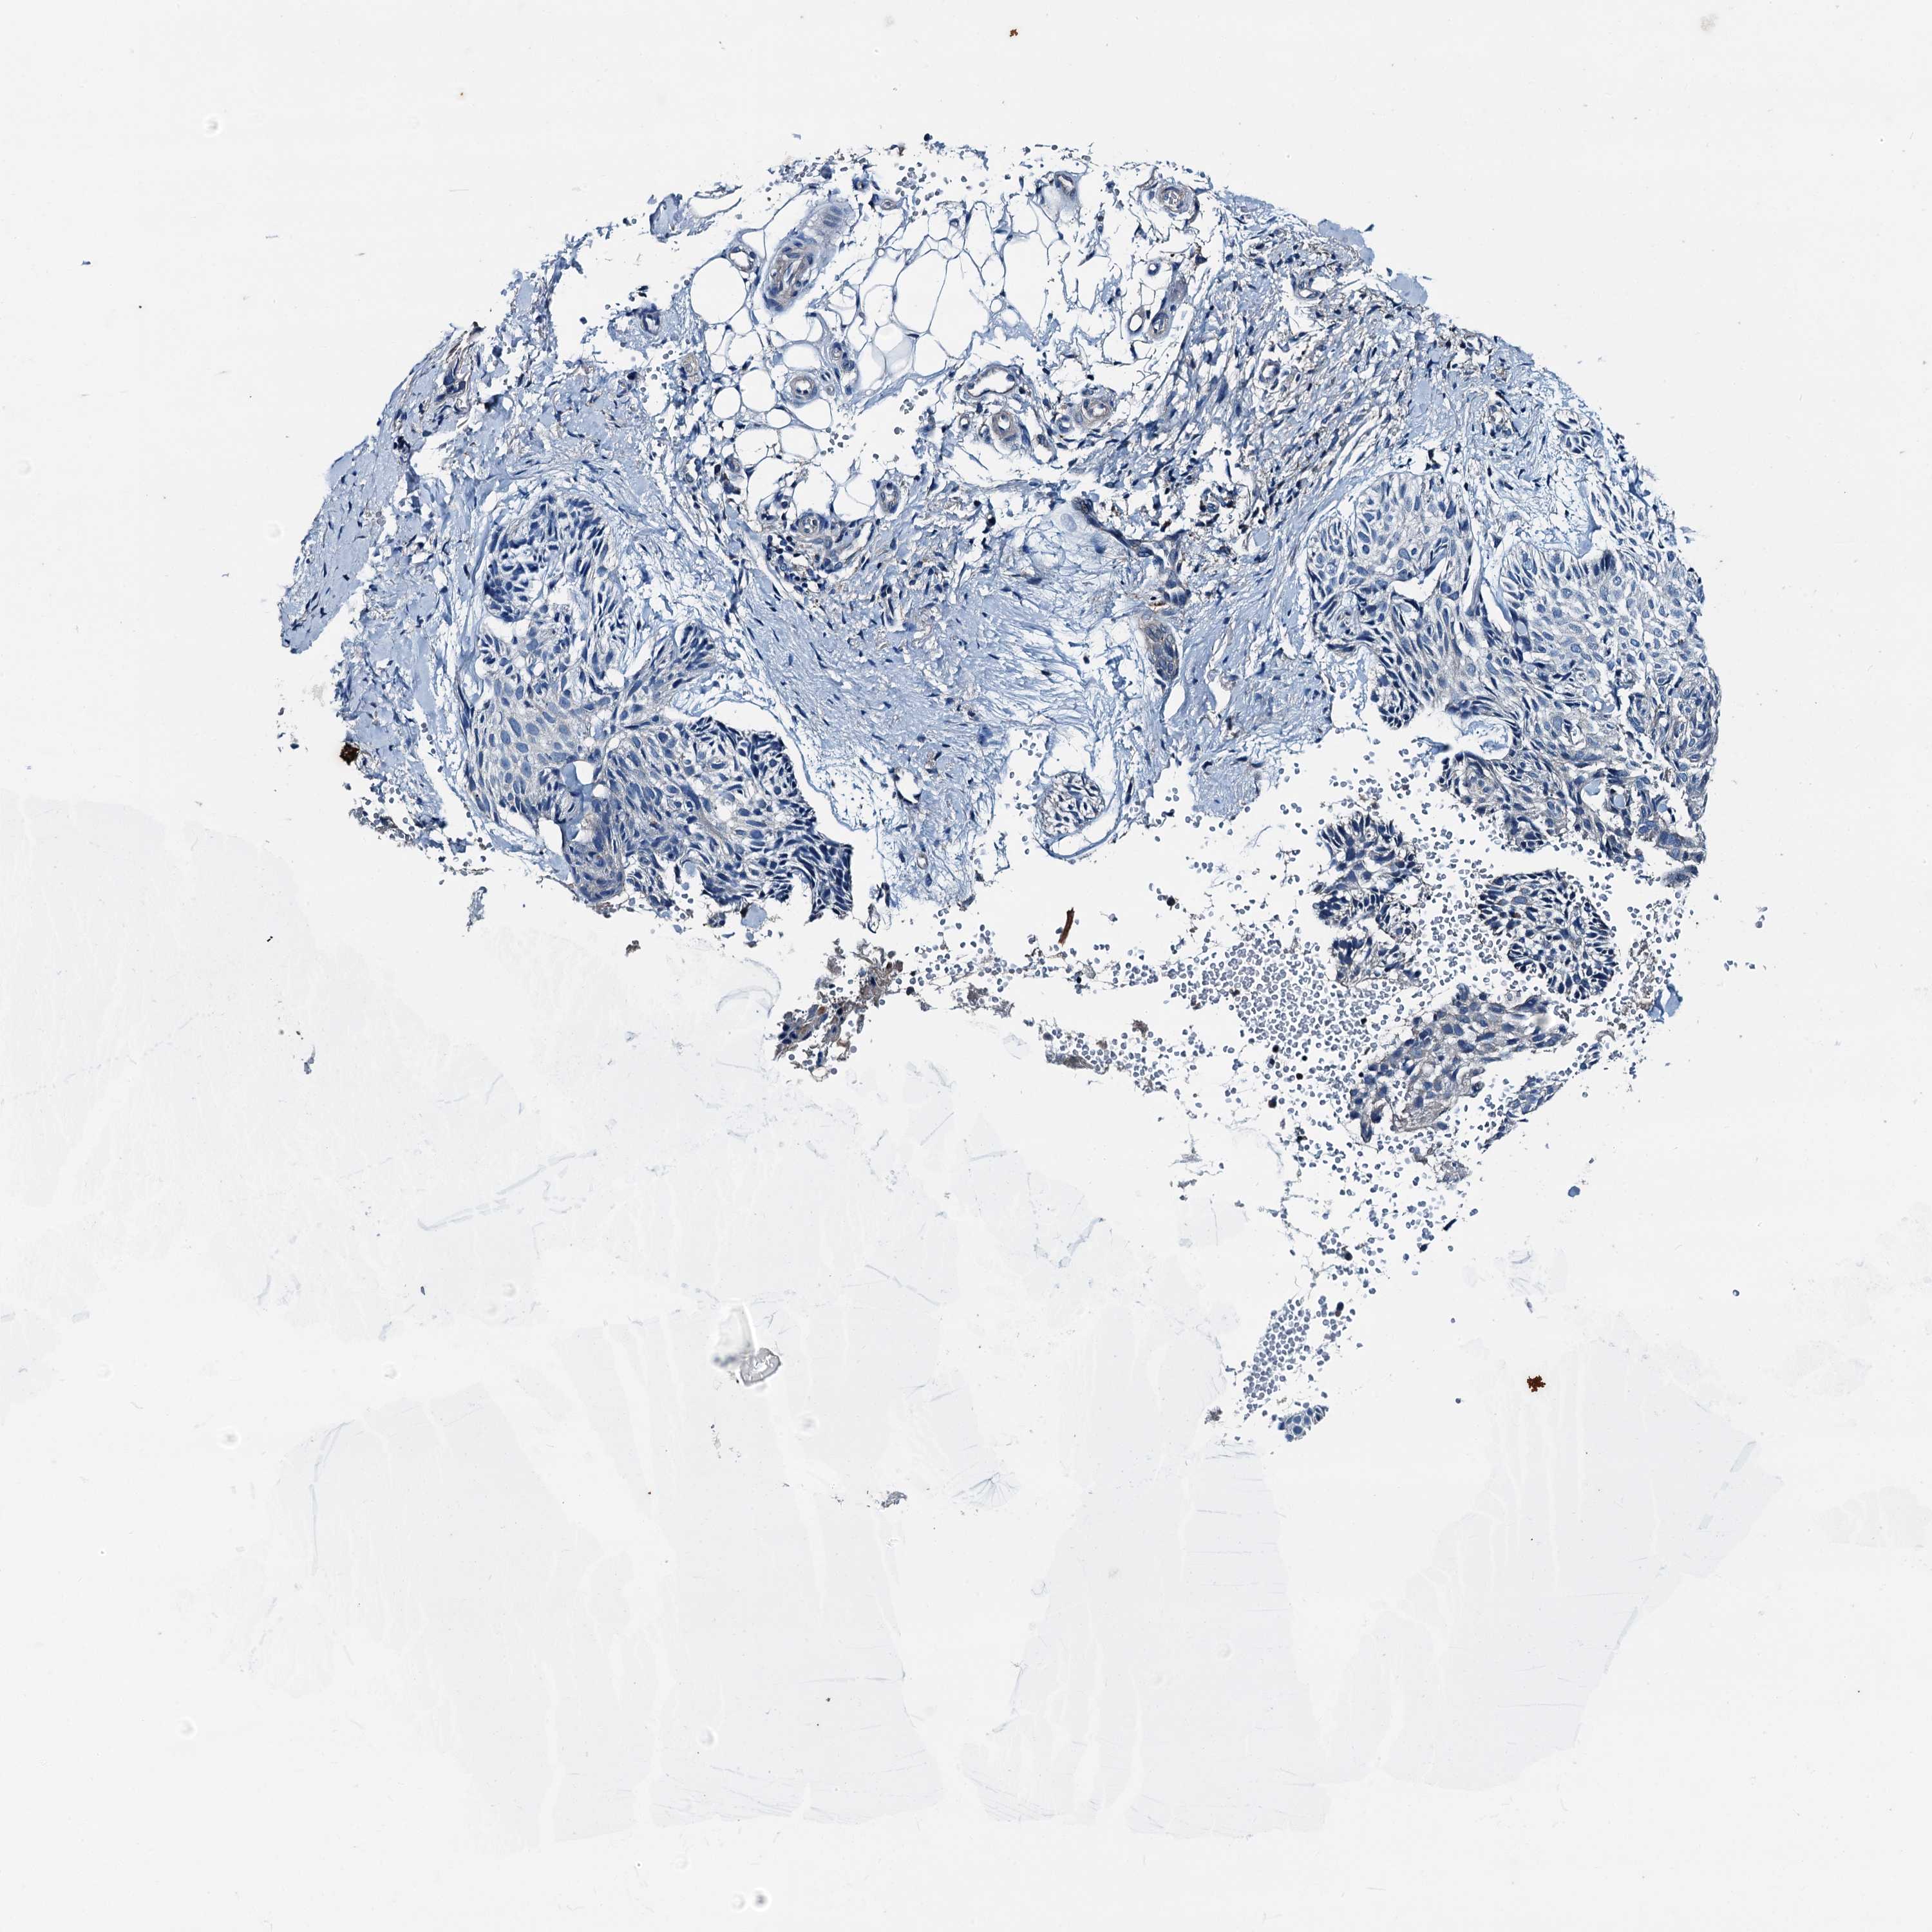

SKIN CANCER - Protein expressioni

A mouse-over function shows sample information and annotation data. Click on an image to view it in a full screen mode. Samples can be filtered based on level of antibody staining by selecting one or several of the following categories: high, medium, low and not detected. The assay and annotation is described here.

Each image is clickable and will lead to virtual microscopy that enables deeper exploration of all samples and also displays staining intensity scores, fraction scores and subcellular localization as well as patient and tissue information for each sample.

Antibody HPA041227

Staining

High

Medium

Low

Not detected

Intensity

Strong

Moderate

Weak

Negative

Quantity

>75%

75%-25%

<25%

None

Location

Nuclear

Cytoplasmic/membranous

Cytoplasmic/membranous,nuclear

Basal cell carcinoma

Squamous cell carcinoma, NOS

Squamous cell carcinoma, metastatic, NOS